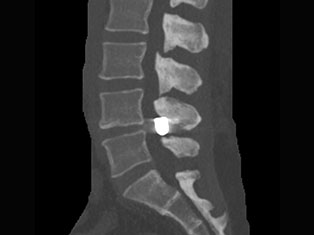

Spinal Tumors

A spinal tumor is a growth that develops within your spinal canal or within the bones of your spine. A spinal cord tumor, also called an intradural tumor, is a spinal tumor that that begins within the spinal cord or the covering.